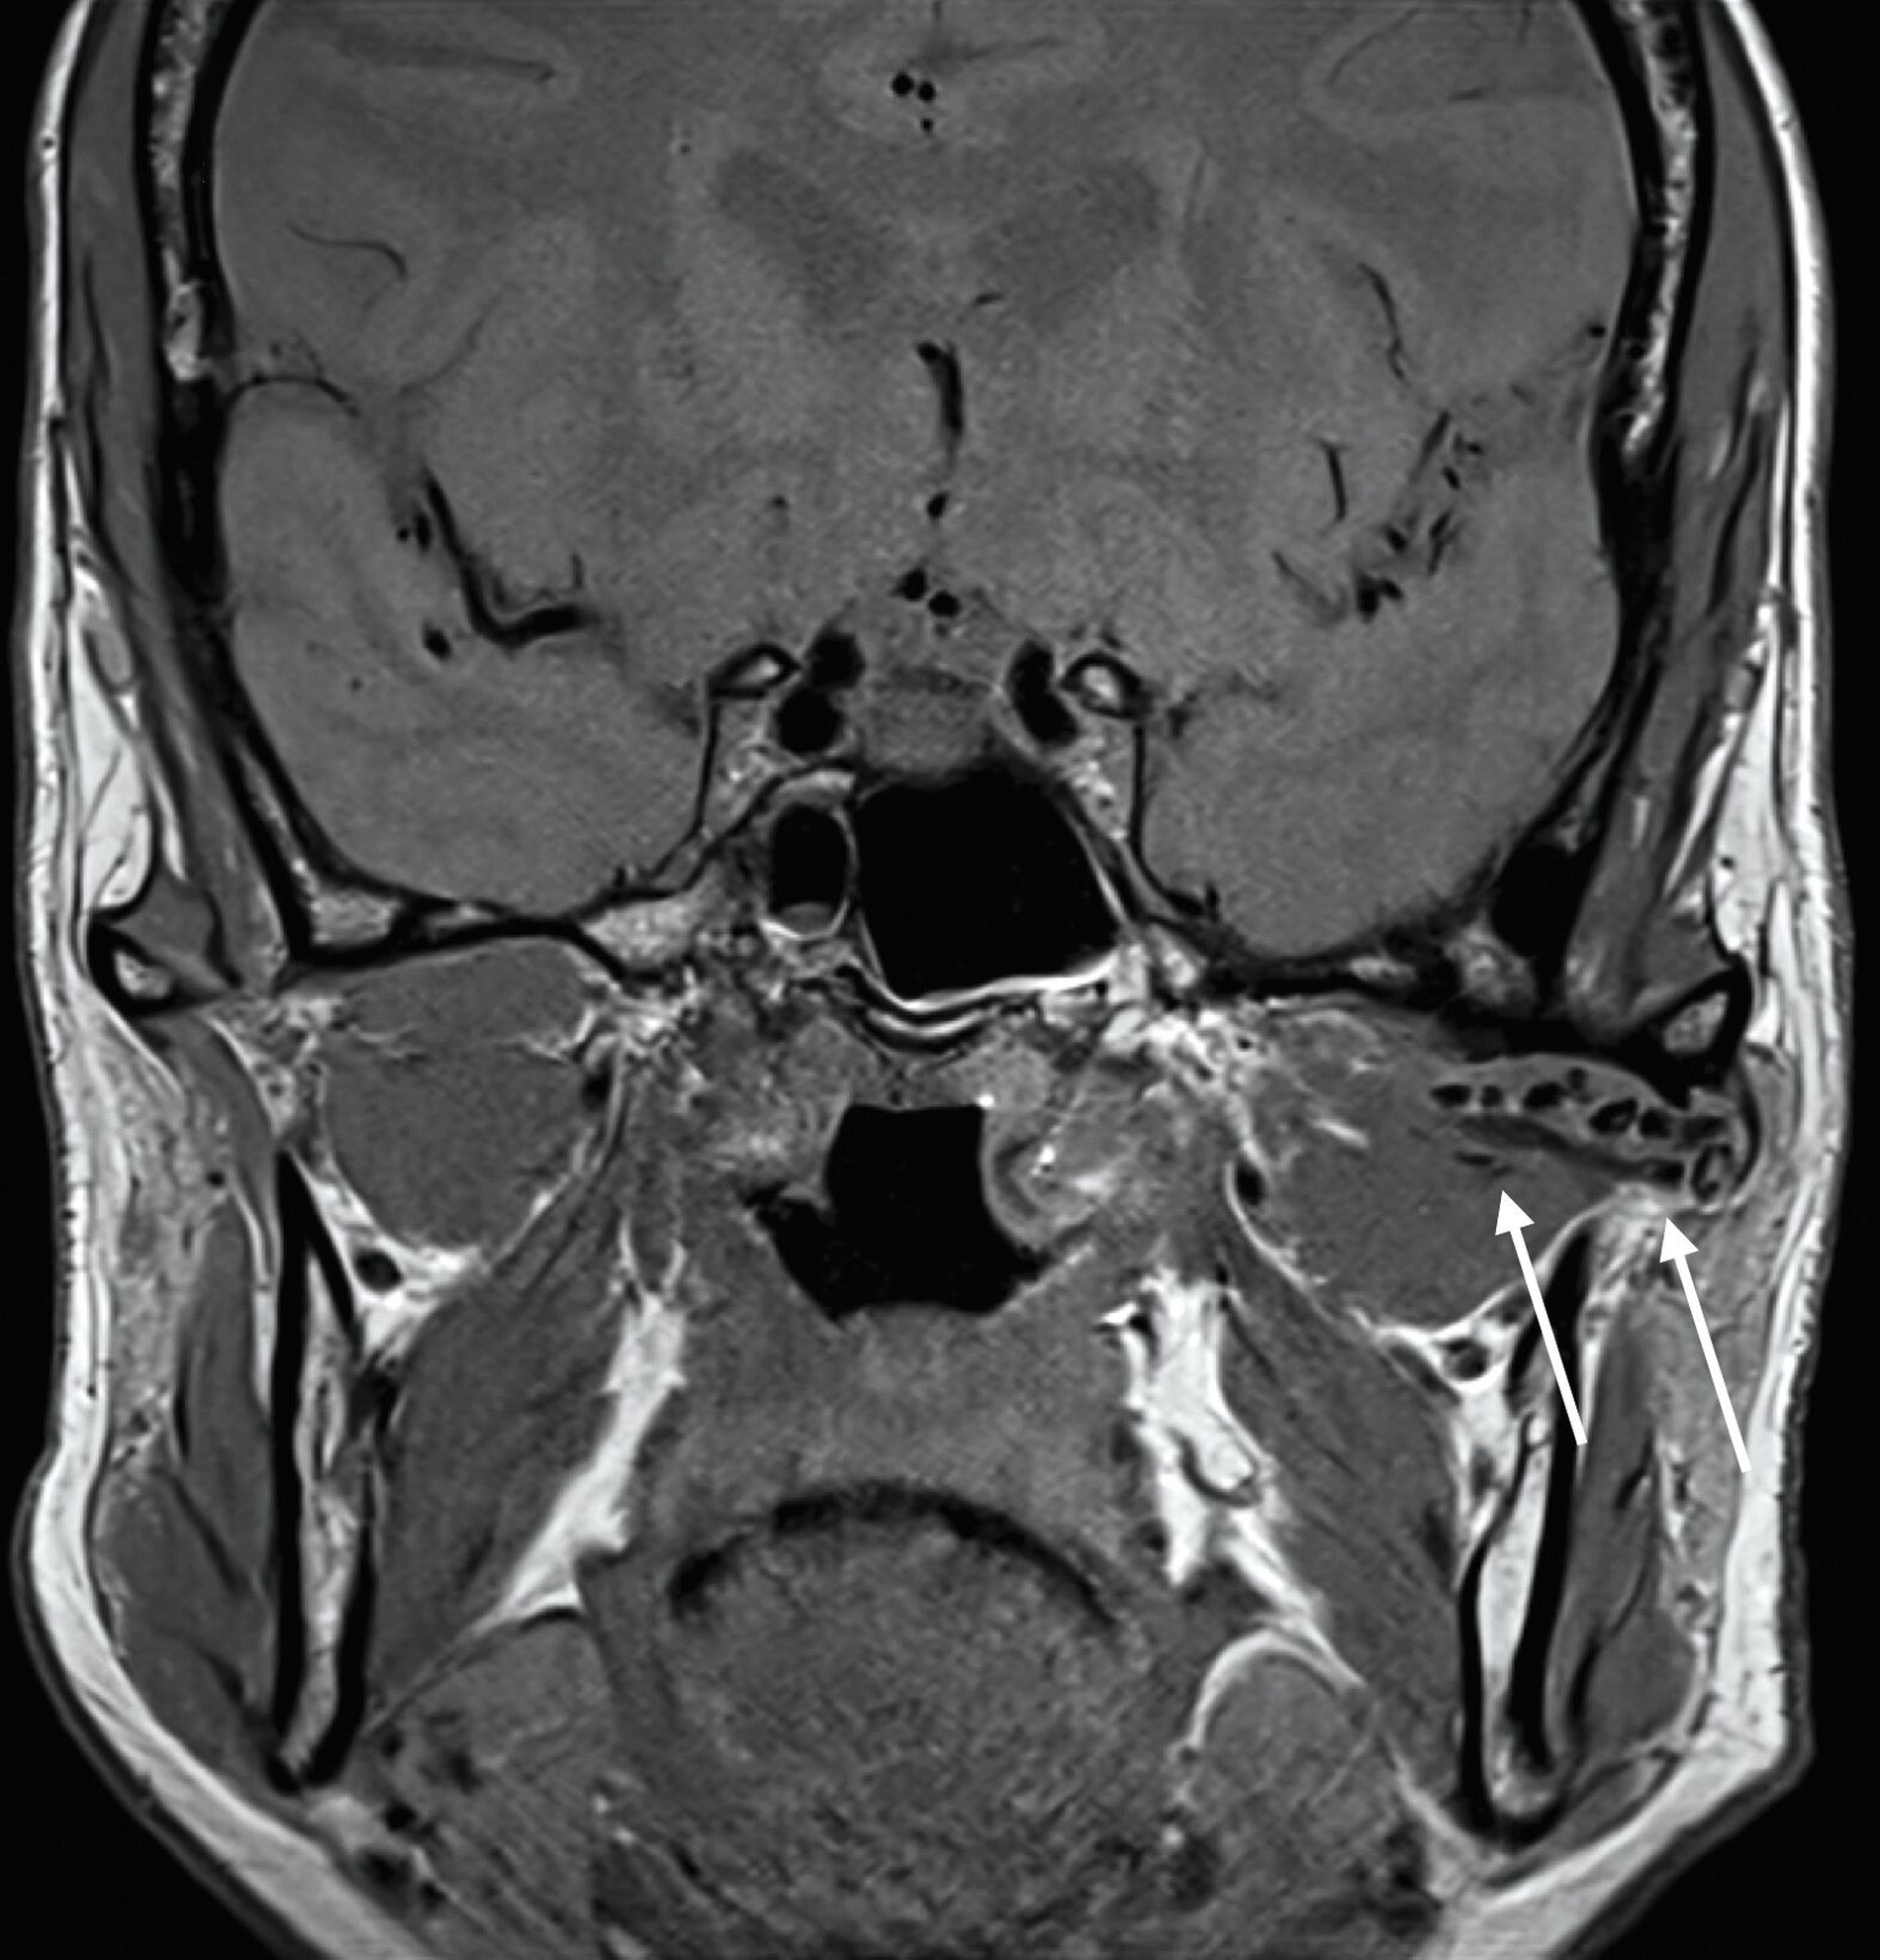

Eine 63-jährige Patientin stellte sich mit einem durch den Hauszahnarzt detektierten Zufallsbefund im linken Kiefergelenk vor. Aufgrund von Mundöffnungsstörungen hatte sie einen Monat zuvor dessen Praxis aufgesucht. Auf der in der Praxis angefertigten Panoramaschichtaufnahme (Abbildung 1) erkennt man opake, rundlich-strukturierte Raumforderungen über dem linken Kiefergelenk.

Die differenzialdiagnostische Abklärung erfolgt nach eingehender Anamnese und klinischer Untersuchung zunächst über die bildgebende Darstellung mittels Magnetresonanztomografie, da die nicht verkalkten Gelenkkörper in der Nativ-Computertomografie (und in der Digitalen Volumentomografie) nicht oder nur sehr spät nachweisbar sind. Die Panoramaschichtaufnahme ist gerade in frühen Phasen der Erkrankung häufig nicht zielführend. In späten Erkrankungsstadien können die Distraktion des Gelenkspalts oder die sekundäre Verkalkung auf das Vorhandensein der Gelenkkörper hinweisen [Reich und Neff, 2022].